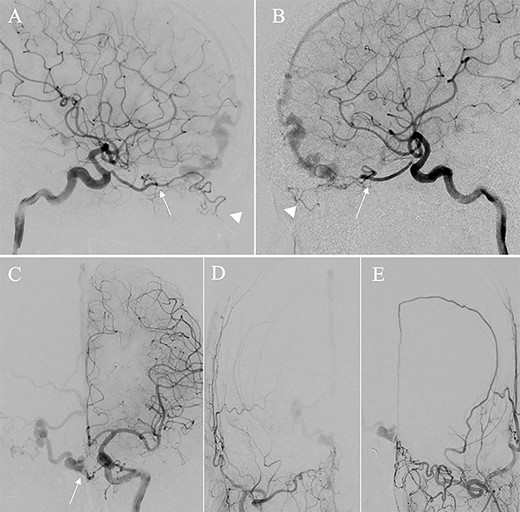

A patient in their 70s with extracranial lymphoma was incidentally found to have ACF–dAVF via head computed tomography and magnetic resonance angiography. Digital subtraction angiography (DSA) confirmed ACF–dAVF with multiple feeding branches, arising from bilateral OphAs, distal IMAs and the left middle meningeal artery (MMA), with cortical venous reflex (Borden type III, Cognard type IV) (Fig. 1). At the patient’s request, we chose endovascular, rather than surgical, treatment. We injected a 20% N-butyl-2-cyanoacrylate (NBCA)–lipiodol mixture into the fistula through bilateral ethmoidal arteries and the left MMA after we placed coils at the terminal branch of the right OphA. However, we could not achieve full penetration into the fistulous connections because of pressure secondary to high flow from the IMA branches, which resulted in incomplete obliteration (Fig. 1). Four months later, we repeated TAE by temporarily reducing nasal blood flow by inserting gauze infiltrated with xylocaine and epinephrine into the nasal cavities. After introducing the guiding catheter, an endonasal surgeon inserted X-ray-detectable surgical gauze infiltrated with 1% xylocaine and epinephrine (1:10 000) into bilateral nasal cavities using a nasal speculum, while paying full attention to avoid damage to the nasal mucosa. Then, we confirmed that the gauzes were placed in appropriate locations in the upper nasal cavity under fluoroscopic guidance. Immediately after insertion, we were able to confirm decreased blood flow from the IMA using DSA (Fig. 2). After this procedure, we navigated a DeFrictor Nano Catheter (Medico’s Hirata, Osaka, Japan) into the terminal branch of the OphA, which was connected to the dorsal nasal artery. Even though there was still a distance from the tip of the microcatheter to the shunt pouch, the NBCA reached the shunt point and penetrated the venous portion (Fig. 3). Follow-up DSA demonstrated complete obliteration of the ACF–dAVF, and blood flow in the nasal mucosa from the IMA branches recovered normally (Fig. 4).

(A) DSA, anteroposterior view, showing complete obliteration of the anterior cranial fossa–dural arteriovenous fistula. (B and C) DSA, anteroposterior view, showing restored blood flow from the internal maxillary artery branches.